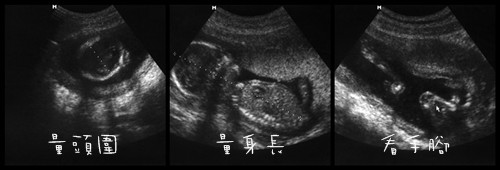

(第二次產檢照,主要是量頭圍與身長,一切都很健康,腦部與心臟也很好)

終於,等到初四產檢,醫生照例做基本檢查,量頭圍,身長...等,

之後,居然一直用超音波檢查棒"桶"我腹部(心裡OS...幹...麻~很痛耶!)

後來是我又請醫生再次確認小牛仔的手腳、腦部與心跳時,他才停止"桶"的動作;

沒想到一切都確認過後,醫生居然又開始"桶"我腹部了,

這時我了解了,問醫生"現在是要確認性別嗎?" 醫生說"是阿!但北鼻的腳弓起來了!"

邊說邊"桶"時,還好北鼻的膝蓋有打開了一點了,

"嗯!胯下有東西,應該是雞雞或是臍帶~不過是小男生的機率很大喔!"